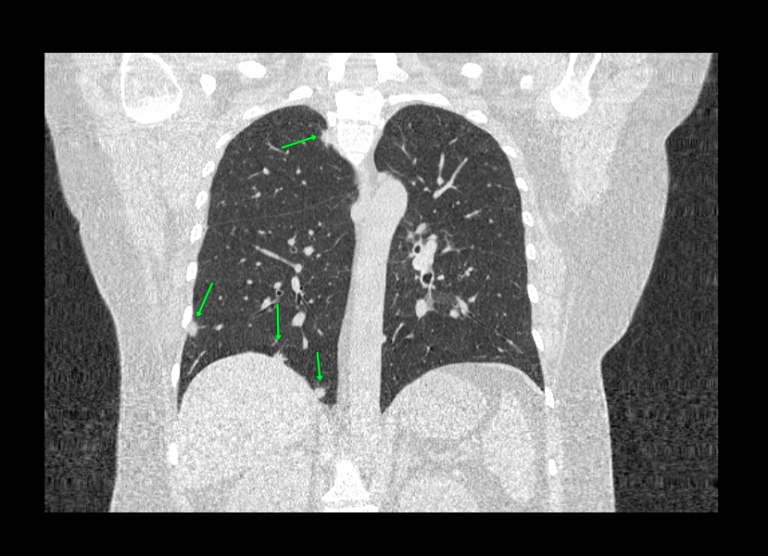

Во время исследования рентгеновская трубка томографа вращается вокруг исследуемой области и производит множество послойных снимков с шагом 0,5-1 мм. Полученные снимки поперечного сечения с помощью компьютерной программы могут быть преобразованы в 3D-изображения исследуемого органа или участка ткани. Это позволяет выявлять практически все заболевания легких на ранних стадиях и назначать своевременное лечение.

В медицинском центре «Доступная медицина» используется современный 128-срезовый компьютерный томограф TOSHIBA AQUILION CXL, на котором проводится сканирование легочной ткани. За счет увеличенного количества детекторов аппарат производит снимки с большой скоростью и минимальной дозой облучения. При этом инновационные цифровые приложения позволяют получить объемные изображения легочной ткани высокой четкости, контрастности и в мельчайших подробностях.

При проведении мультиспиральной КТ легких можно диагностировать различные заболевания, в том числе: